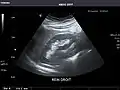

Right kidney

Kidneys: Right and left kidneys measure 11.5 cm and 12 cm in length respectively. No hydronephrosis. Small left lower pole kidney cyst.